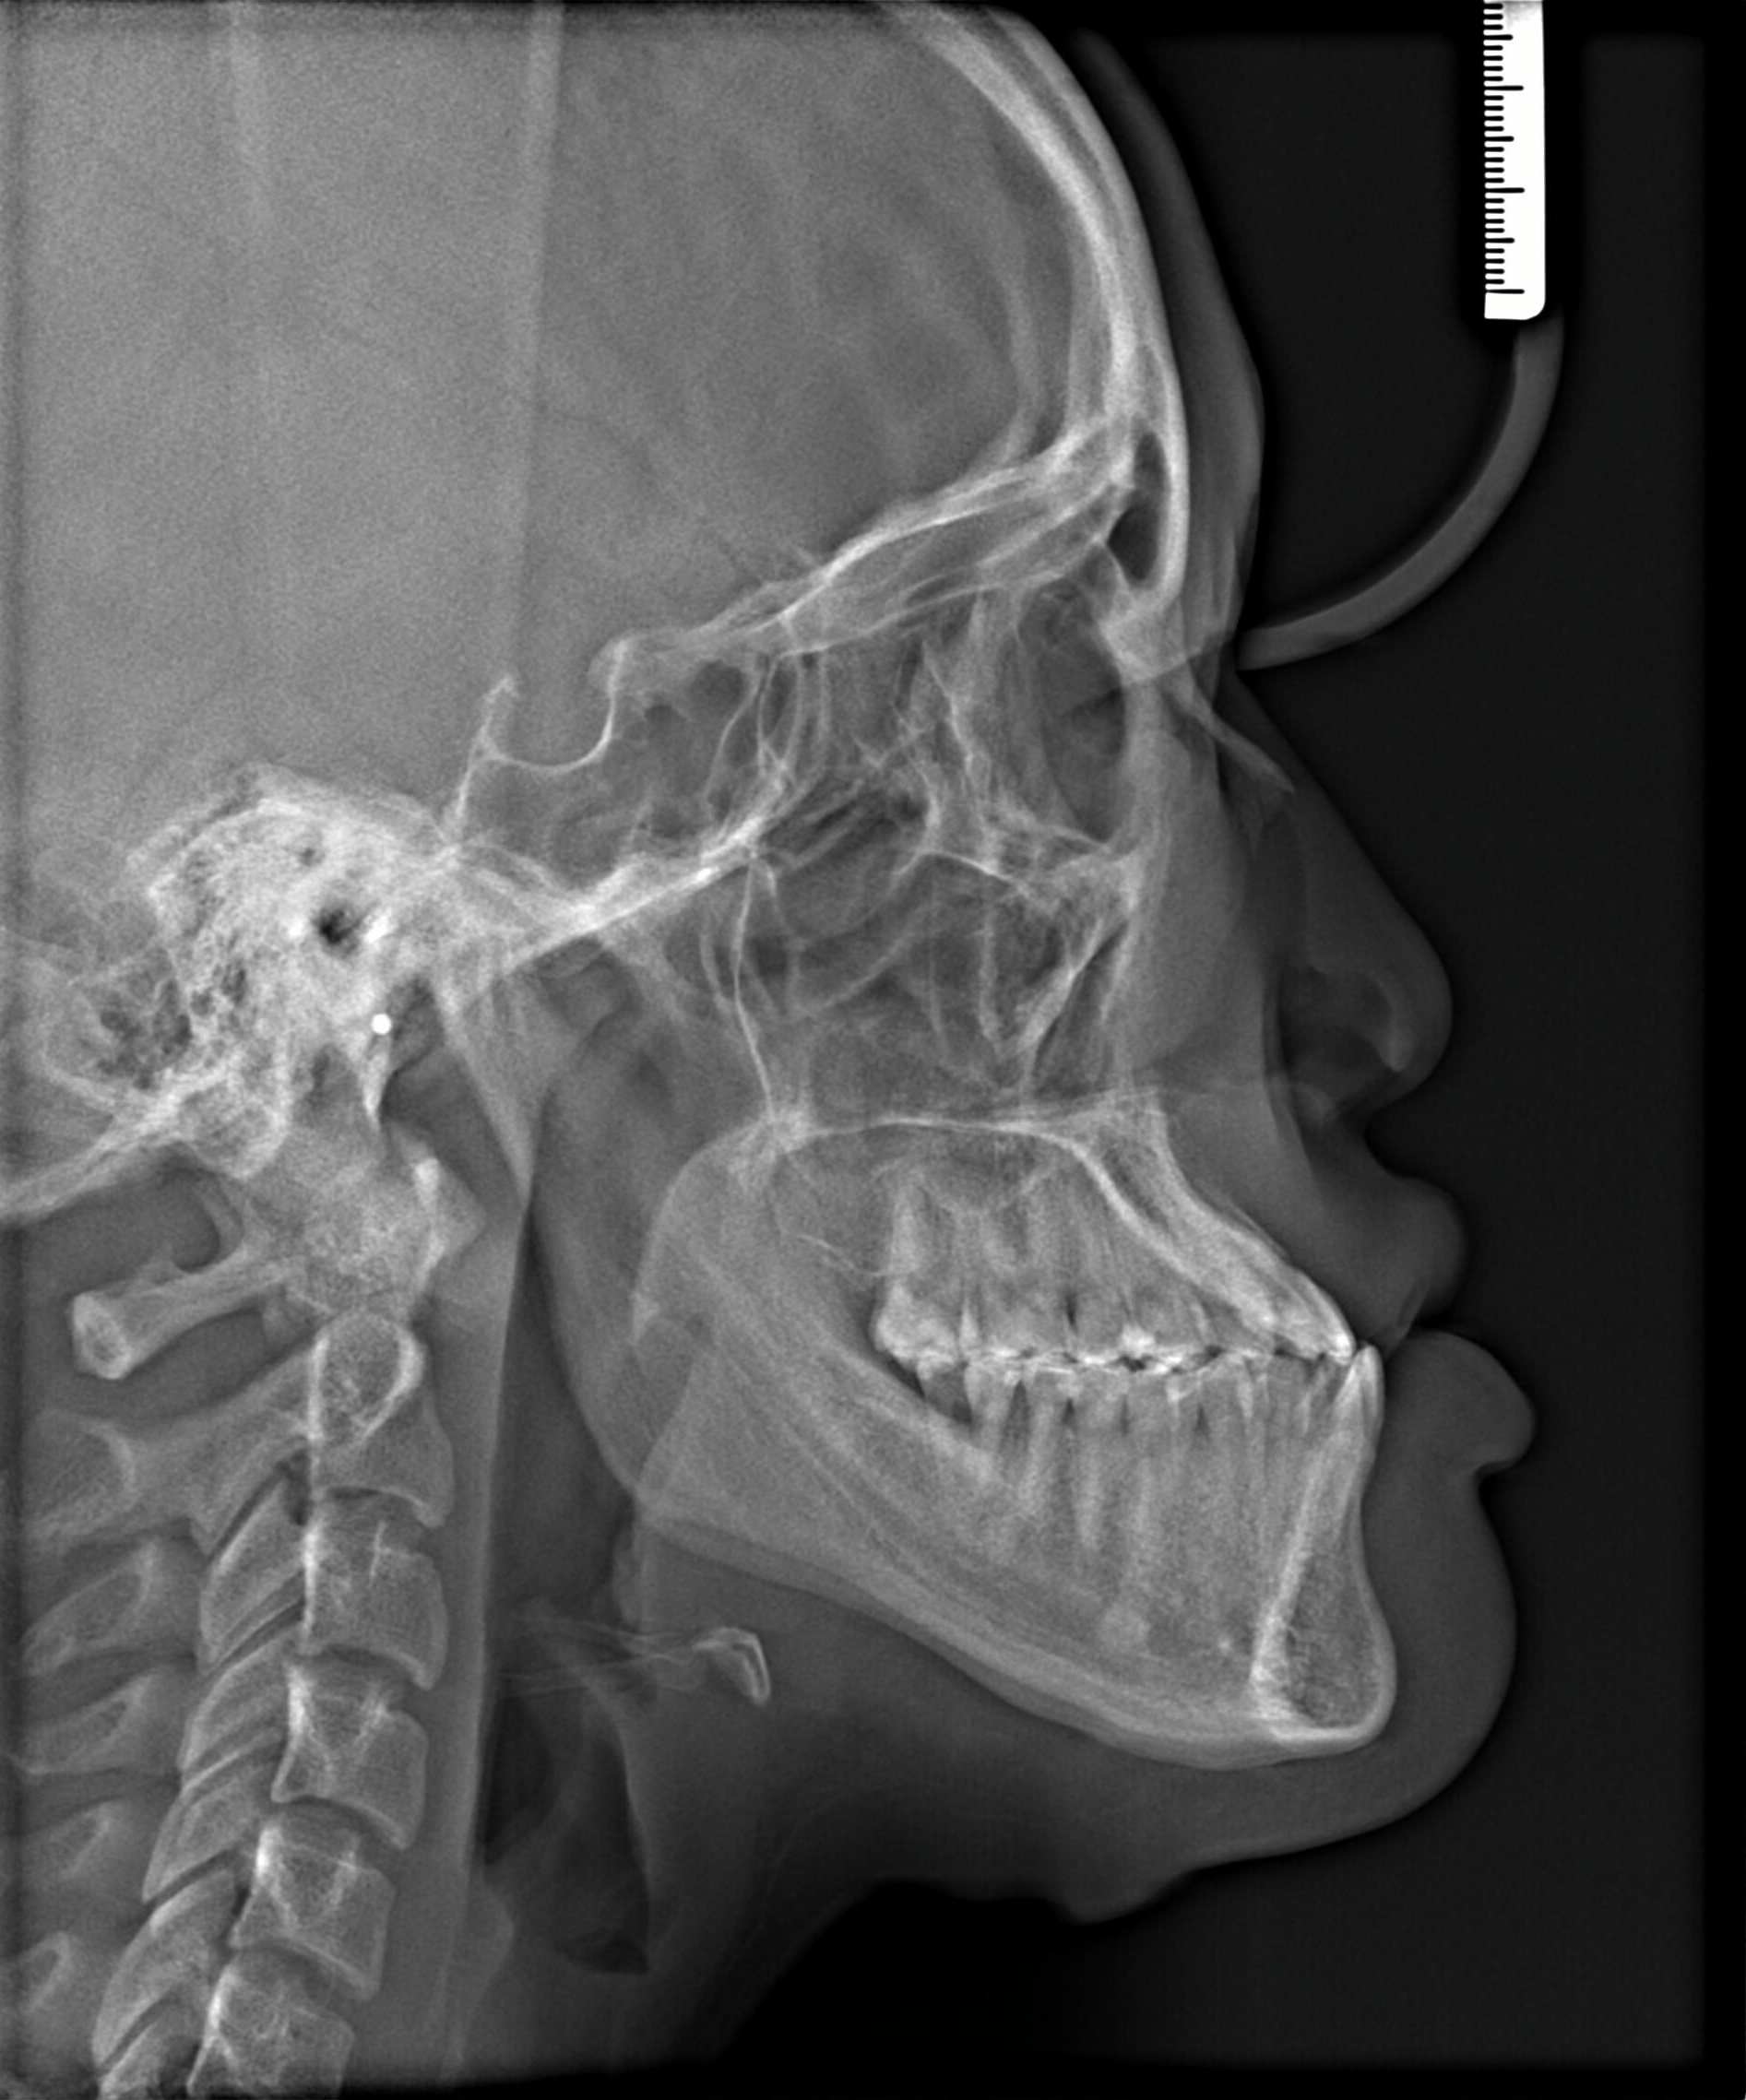

After Metal Self-Ligating Braces & Orthognathic Surgery: The Surgical Comeback smile results by Las Vegas Orthodontist Dr. Saoly Benson. Treatment approach: this transformation was designed with intention. After

After orthodontic x-ray: Cephalometric profile after Metal Self-Ligating Braces & Orthognathic Surgery showing skeletal correction by Dr. Saoly Benson. After

This case began with a severe skeletal imbalance that braces alone could not correct. The patient presented with a significant Class III bite, asymmetric mandibular prognathism, anterior crossbite, and midline deviation. Because the jaw relationship was the root of the problem, a combined orthodontic and surgical approach was required to achieve the best stable, long-term result.

This transformation was designed with intention. Dr. Benson used braces to sculpt alignment and prepare the bite, then collaborated with an oral surgeon to reposition the mandible through orthognathic surgery. The result: a stable bite, restored facial balance, and symmetry achieved.